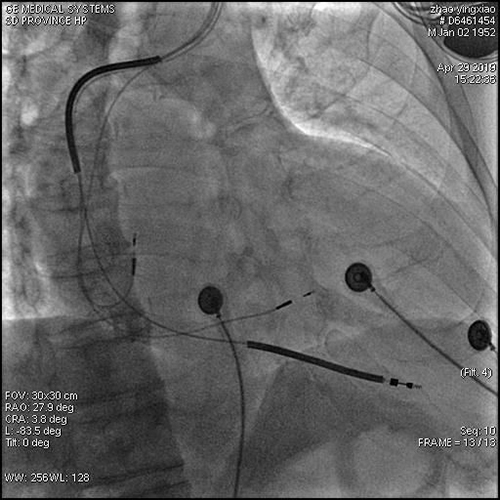

术后影像:RAO体位

术后影像:LAO体位